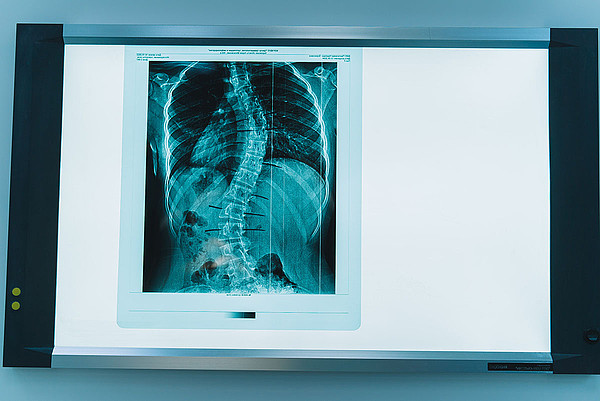

19102022-39.